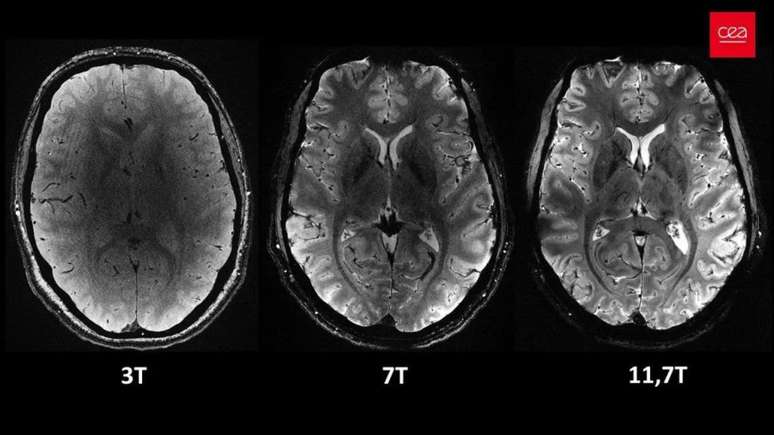

A Comissão de Energia Atômica da França (CEA) divulgou imagens inéditas de alta precisão do cérebro humano, obtidas através do scanner Iseult, considerada a máquina de ressonância “mais poderosa do mundo“.

O scanner, com uma intensidade de campo magnético de 11,7 teslas, adquiriu as imagens em apenas 4 minutos, proporcionando detalhes anatômicos e de atividade cerebral que não seriam alcançados em outros aparelhos.